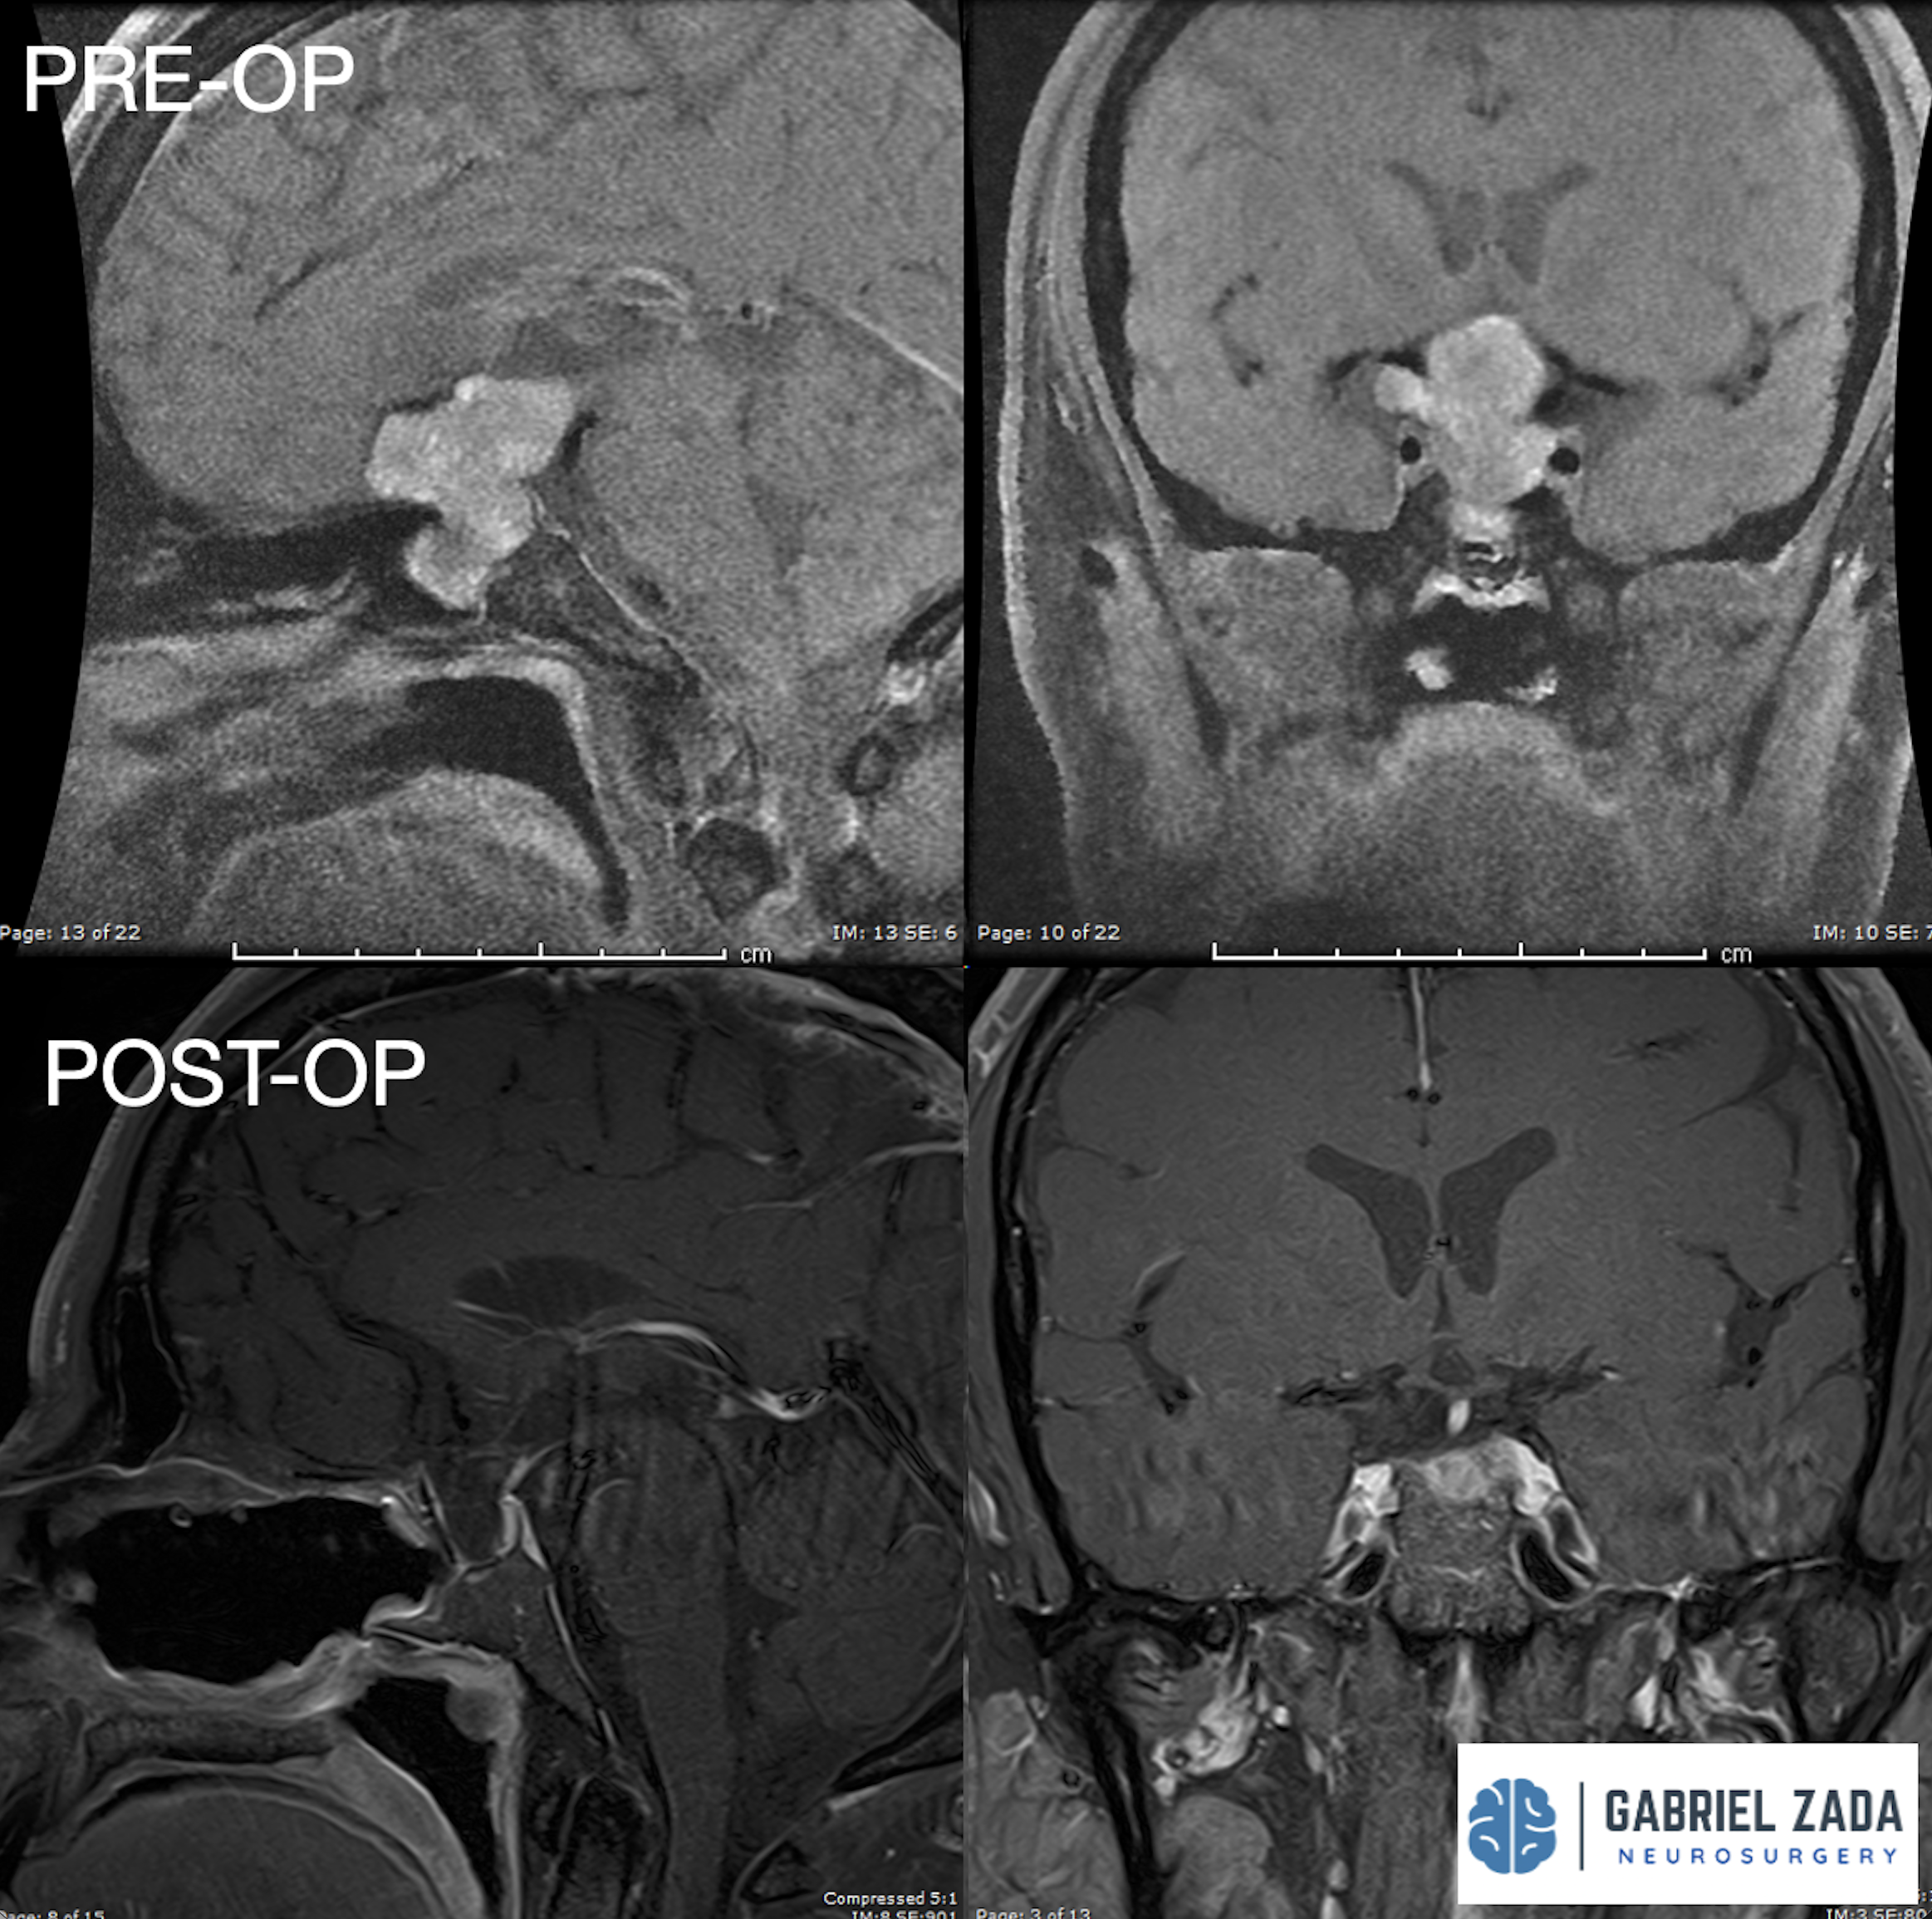

Explore this comprehensive gallery featuring pre‑ and post‑operative imaging of patients with skull‑base tumors treated by Gabriel Zada, MD, MS, FAANS, FACS. These cases highlight Dr. Zada’s expertise in advanced neurosurgical techniques and outcomes.

*Representative cases shown for educational purposes. All images de-identified. Individual results vary.